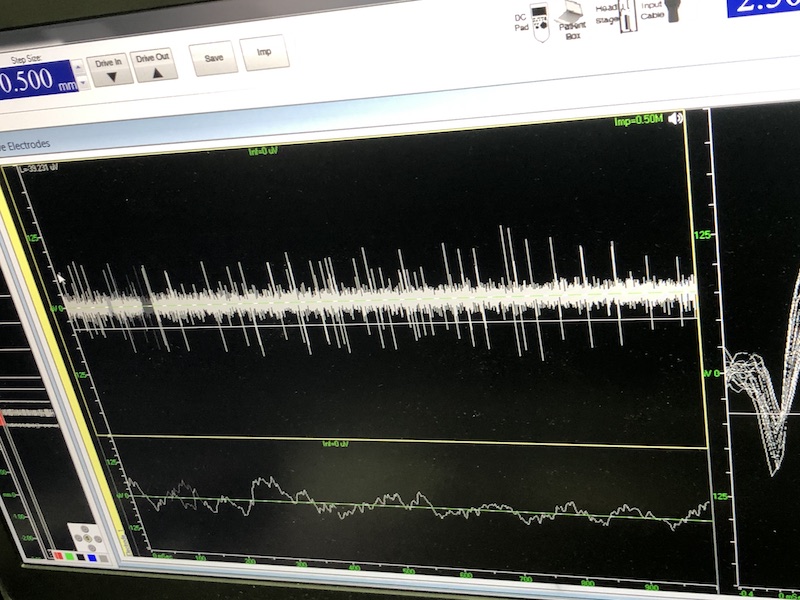

與此同時(shí),檢測(cè)電極實(shí)時(shí)記錄電極末端每一點(diǎn)處的電信號(hào),當(dāng)電極逐漸接近手術(shù)規(guī)劃靶點(diǎn)時(shí),借助電信號(hào)的特征,醫(yī)生可以判斷電極是否已經(jīng)沿長(zhǎng)軸植入患者顱內(nèi)的目標(biāo)核團(tuán),以及植入的準(zhǔn)確長(zhǎng)度。下圖中,檢測(cè)信號(hào)屬于典型的核團(tuán)信號(hào),證明電極已經(jīng)抵達(dá)相對(duì)理想的植入位置,記錄下此刻的位置后,即可在相應(yīng)位置植入刺激電極。

alt text

檢測(cè)核團(tuán)信號(hào)